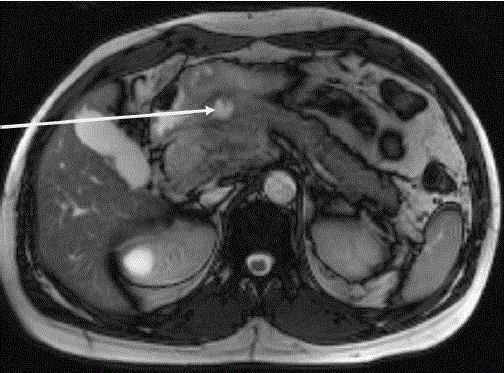

Figure 3. MRI showing a posterior lesion penetrating into the pancreas (arrow).